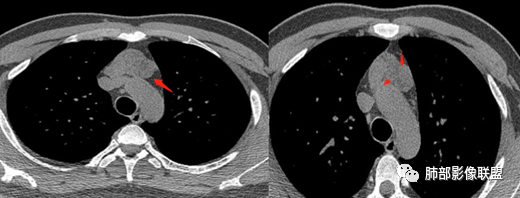

南边分析-征象标注

年轻男性,双下肌乏力,可惜没交代是啥手术,是不是前纵隔病变手术。

1、一般这样的乏力:1.神经系统问题;2.胸腺问题。

* 整个形态就是胸腺的形态,定位在前纵隔,胸腺病变应该可以。26岁男性,这么年轻,胸腺源性肿瘤几率比较低,

1.非肿瘤性病变2.其他来源肿瘤性病变

2、下半部分,形态自然,边缘稍膨隆,内部密度实性夹杂稍低密度影,而且是线样低密度影,比较自然走形,支持胸腺组织增生或残留。如果其他肿瘤所致,应该是边缘膨隆,类圆形,内部密度均匀,或部分区域坏死,或者结节状灶之间间隔。所以这个首先:胸腺增生或残留应该有。

* 部分区域边缘平直、稍凹陷,部分密度较低,边缘稍膨隆。

* 部分密实。因为没有增强,附近血管分不开,内部密度差不是那么明显,但是有密度差。提示:内部组织结构有变化,不是单一的组织结构。

考虑:1.发生过炎症或内部组织增生程度不一,导致各区域密度差

2.不除外合并其他病变:

①可能合并囊变

②目前的资料不能排除合并其他肿瘤性病变的可能性

**综上所述**

1.胸腺增生或残留应该可以肯定

2.病灶有过炎症或囊肿合并炎症

3.不能除外合并其他肿瘤